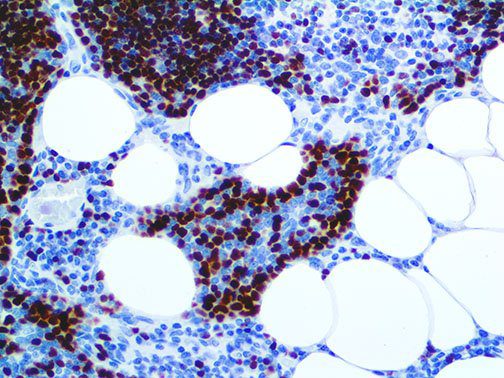

It is the ICU physician who is most likely to witness one of the deadliest manifestations of the abnormal immunological response, the cytokine storm syndrome (CSS). This response is also referred to by some as the cytokine release syndrome (CRS). CSS is characterized by continuous activation and expansion of macrophage and lymphocyte populations, which secrete large amounts of cytokines, causing the cytokine storm. This massive cytokine release is akin to hemophagocytic lymphohistiocytosis (HLH) disease, a syndrome characterized by initial unchecked and persistent activation of cytotoxic T lymphocytes and NK cells.

Clinical and laboratory manifestations of HLH include fever, enlarged liver and/or spleen, neurologic dysfunction, coagulopathy, liver dysfunction, cytopenias (i.e., low levels of erythrocytes, leukocytes, and/or platelets), hypertriglyceridemia, hyperferritinemia, hemophagocytosis, and eventually diminished NK cell activity as the immune system becomes progressively paralyzed. HLH can be familial (primary HLH) or secondary to another disease process (sHLH), such as rheumatic disease, in which it is referred to as macrophage activation syndrome (MAS, characterized by elevated ferritin).